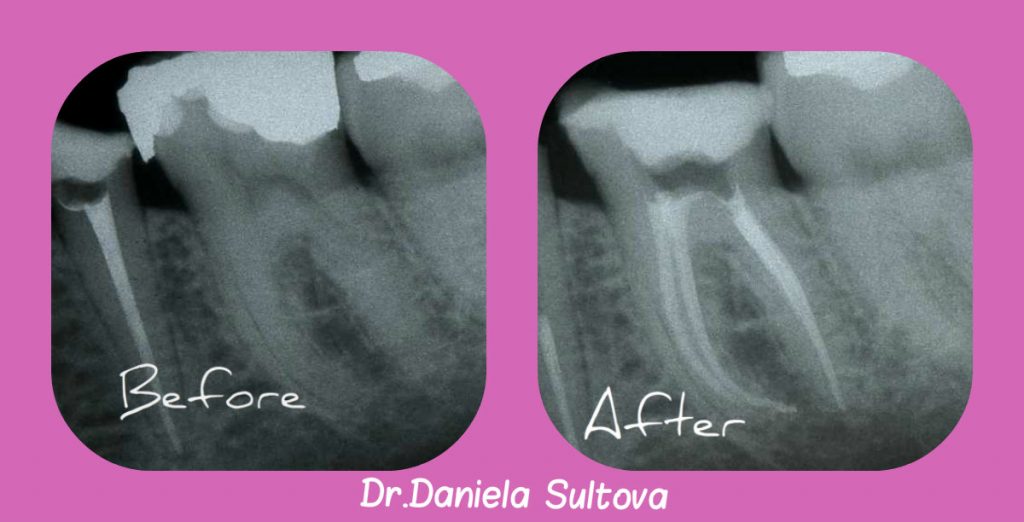

Лечението включва кореново лечение – механична и химична обработка на зъба, последвани от запълване на каналите. Периодично тези зъби се проследяват с рентгенови снимки.

Лечение на пулпит на зъб 46 с голяма кривина на извивката